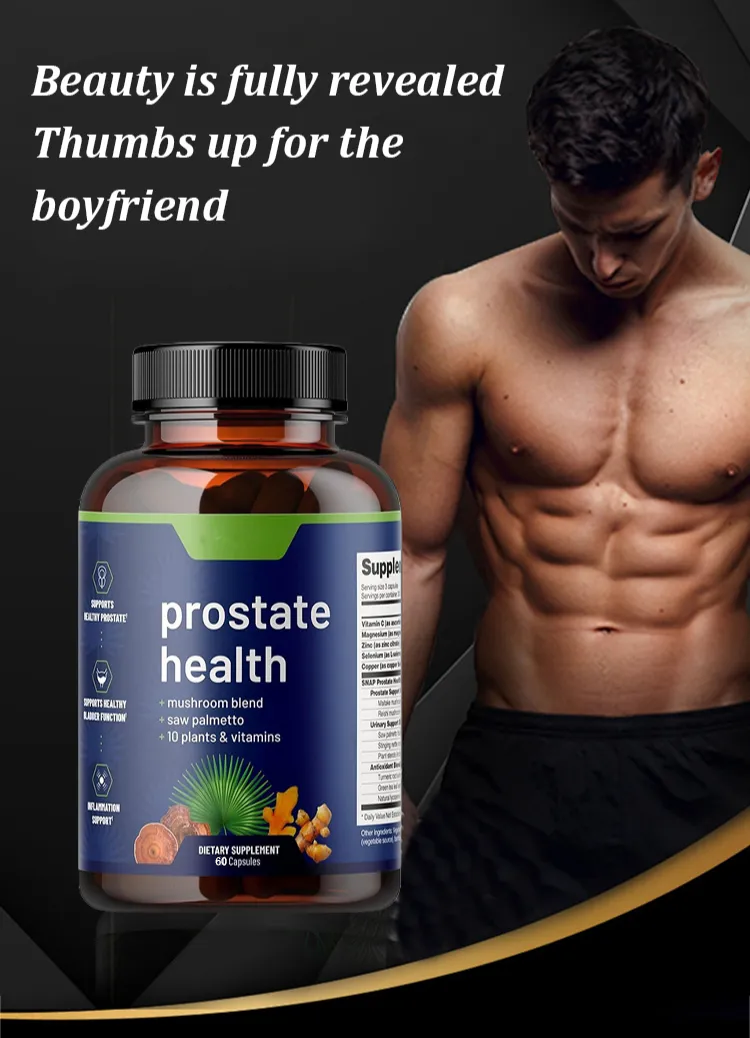

Lancetswell™ Saw Palmetto Prostate Health Supplement are meticulously crafted to provide comprehensive support for prostate health and alleviate the bothersome symptoms often associated with prostate issues.

Key Features & Highlights

🔹Comprehensive Prostate Support

🔹Reduced Inflammation

🔹Hormonal Balance

🔹Nerve Health Support

🔹Enhanced Urinary Function

🔹Antioxidant Protection